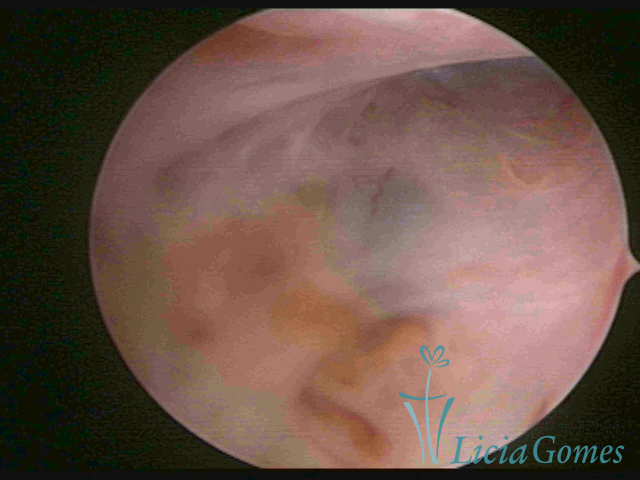

ADENOMIOSE

É a presença de tecido endometrial na camada muscular do útero

A vídeo-histeroscopia permite diagnosticar às lesões próximas às camadas miometriais superficiais, próximo ao endométrio visualizando lesões de coloração violácea, circunscritas, ou acastanhadas com conteúdo achocolatado.